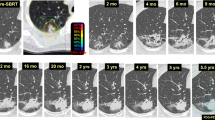

Based on our experience and data from the literature, it is sometimes difficult to distinguish between a mass-like consolidation and a tumor recurrence using CT imaging at one time point. Serial imaging studies and correlation of the SBRT isodose distribution and CT changes are important in order to determine whether the imaging changes are related to fibrosis or tumor recurrence. In general, fibrosis induced by ablative radiation doses tends to stabilize after 1–2 years. Figures 1 and 2 demonstrate the serial CT changes that occurred after SABR for medically inoperable NSCLC.

Given the ablative nature of SABR, the inflammatory and fibrotic reactions in the lung parenchyma are more intense after treatment [3]. Based on the observations from multiple studies, CT findings of radiation-induced injury usually do not appear within the first 6 weeks after SABR [7]. Early radiation injury, caused by inflammation, starts to occur 2–6 months after treatment. Different patterns of changes on CT have been observed by various groups [3–7]. Late radiation injury starts to develop 6–9 months after treatment, and similar to early effects, different injury patterns can occur. One of the late injury patterns, mass-like consolidation, can occur in a significant proportion of patients after SABR and is frequently the source of confusion [3, 10, 11]. Most of the cases of mass-like consolidation represent dense fibrosis rather than tumor progression [3, 10]. The area of consolidation frequently does not correspond precisely to the treated PTV and may continue to shift in position within 1 year after treatment [9]. In general, fibrotic changes should stabilize after 1–2 years. However, continued changes may occur even after 2 years [13]. When there is growth of size of the mass consolidation, a bulging margin, loss of air bronchogram, or pleural effusion, tumor progression should be suspected [12].